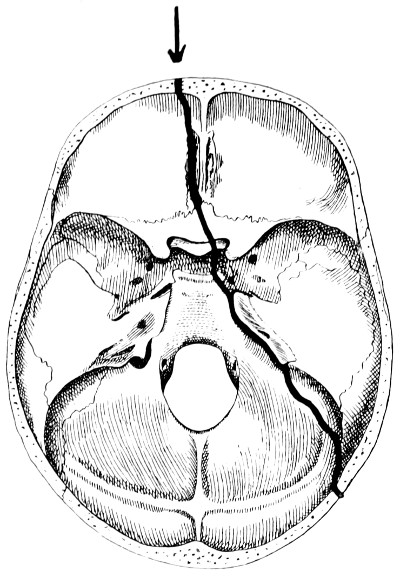

| 28. Illustrating the lines along which forces received on the vault are transmitted to the base | 69 |

| 29 A and B. The base of the skull and the base as seen on transillumination | 70, 71 |

| 30. Plan of the base of the skull | 77 |

| 31. To illustrate the relation of basic fractures to cranial nerves | 81 |

| 32-37. The lines pursued by basic fractures | 83-8 |